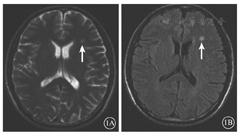

患者男,48岁。因"右眼视力丧失5 d、左眼视力骤降3 d"于2016年6月23日收住我科。患者自6月4日起无明显诱因出现发热,当地医院治疗不理想,体温反复。6月13日以"发热原因待查"收住我院呼吸内科,行相关检查诊断为肺部感染。6月15日因患者出现嗜睡状态转至我院神经内科。检查见认知功能异常、颈项强直、脑膜刺激征(-)。脑脊液无色透明,压力正常;白细胞计数43×106个/L,分类以单核细胞为主,三磷酸尿苷升高,氯化物轻度降低;脑脊液培养、涂片正常。头颅MRI可见脑实质受损(图1)。诊断为病毒性脑炎。给予抗病毒及抗炎治疗后认知障碍逐渐好转。6月18日患者右眼视力骤降请我科会诊。眼底检查见右眼视盘水肿,黄斑中心凹反光不清。6月21日患者左眼视力明显下降再次请我科会诊。右眼视力无光感,瞳孔散大,对光反射消失,晶状体点状混浊,玻璃体混浊(++),可见絮状漂浮物;视盘颜色淡,边界欠清晰,静脉纡曲扩张,视网膜颜色苍白,可见灰白色渗出及出血点,黄斑中心凹未见反光(图2A)。左眼视力数指/10 cm,矫正视力0.08;角膜6~ 9点时钟位可见一乳白色陈旧性瘢痕,瞳孔对光反射迟钝,晶状体点状混浊,玻璃体混浊(+),可见尘状漂浮物;颞下方周边视网膜部分血管白鞘形成,未见渗出和出血,黄斑中心凹未见反光。双眼眼压正常。B型超声检查,玻璃体混浊征像。荧光素眼底血管造影(FFA)检查,右眼视网膜动静脉充盈迟缓,可见荧光素渗漏、新生血管及无灌注区(图2B )。考虑诊断"双眼急性视网膜坏死综合征(ARN)" 。给予更昔洛韦250 mg静脉滴注,2次/d等抗病毒治疗,同时辅以改善循环及对症支持治疗。同时请中山大学眼科中心会诊后,治疗方案改为更昔洛韦500 mg静脉滴注,2次/d;口服泼尼松50 mg,1次/d,10 d后减量;依据病情予视网膜变性坏死区与正常视网膜交界处行激光光凝。修正诊断为"病毒性脑炎合并双眼ARN" 。经3 d治疗后眼底检查可见左眼颞下方4点时钟位周边视网膜多个裂孔形成,给予左眼激光光凝治疗;右眼辅以玻璃体腔注射更昔洛韦治疗。6月27日眼底检查,左眼颞下方病变区扩大,再次行激光光凝治疗。7月1日眼底检查,右眼视网膜转为黄白色局限渗出病灶;左眼颞下方周边视网膜可见激光光凝斑,病变范围无变化(图3)。病情稳定后出院。出院后2个月复查,脑脊液各项指标恢复正常。右眼视力光感,视盘颜色苍白,黄白色渗出病灶明显吸收,黄斑中心凹反光可见。左眼视力0.12,矫正视力0.25;视盘颜色偏淡,黄白色渗出病灶明显吸收,可见激光光凝斑,黄斑中心凹反光不清。